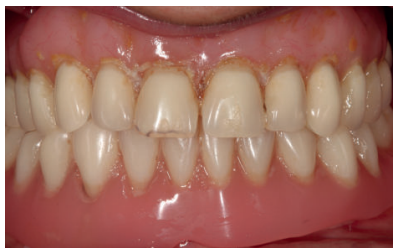

Presentamos el caso de una mujer de 67 años que acude a la consulta para solicitar un tratamiento que mejore la estética y la funcionalidad de las prótesis removibles que porta. En la radiografía panorámica inicial se observan dos implantes en la región anterior mandibular que actualmente no están formando parte de la rehabilitación, que en algún momento sostuvieron una barra para una sobredentadura (Figura 2). En la imagen de sonrisa e intraoral podemos ver la prótesis removible superior e inferior deteriorada y con zonas fracturadas (incisivo central superior derecho) (Figura 3). Al retirar las prótesis podemos observar los implantes con dos tornillos fracturados en su interior (Figura 4).

Podemos observar la comparación entre el estado inicial y el resultado final, que satisface los deseos estéticos y funcionales de la paciente y además recupera la dimensión vertical perdida con las prótesis removibles (Figuras 27-30).